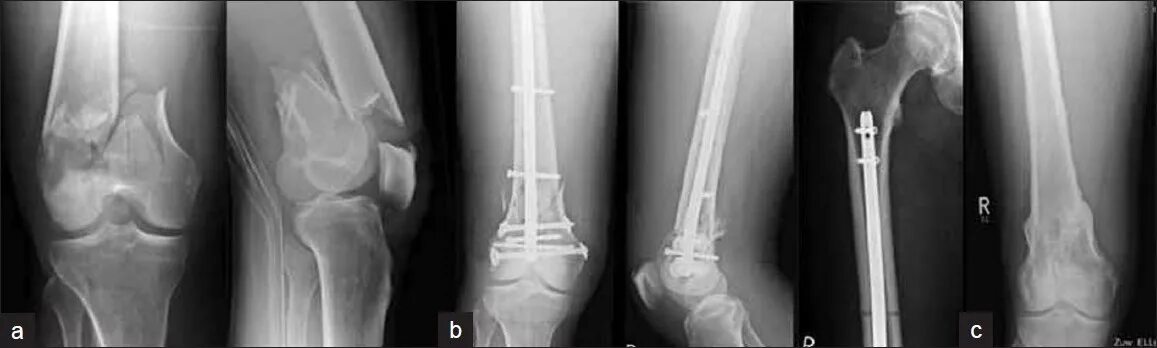

Перелом 1 3 бедра